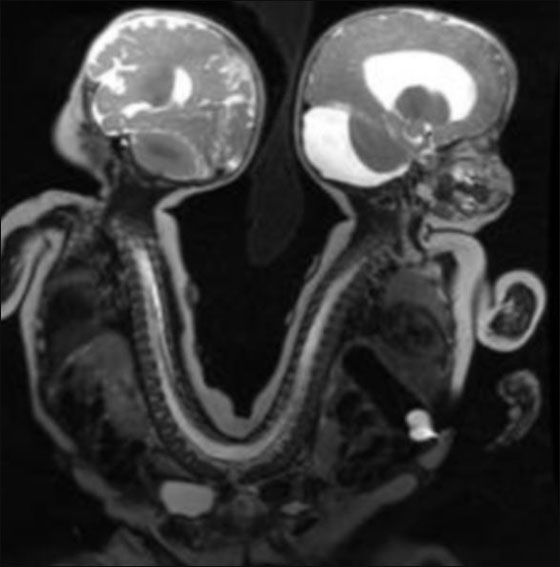

نجا توأمان سياميان بأعجوبة بعد عملية فصل بينهما، بعد ان كان عامودهما الفقريان ملتصقان طيلة فترة حمل والدتهما بهما، تضاف اليها ثمانية اشهر بعد ولادتهما، بحيث كانت فرصتهما للبقاء على قيد الحياة ضئيلة جدا. فتحدى التوأمان البالغان من العمر ثمانية اشهر كل الصعاب ونجيا من عملية فصلهما التي دامت 13 ساعة.

يواصل جشوا ويعقوب سابتيس من مدينة ممفيس بولاية تينيسي، صراعهما على الحياة تحت أعين الأطباء، لكنهما تغلبا على العقبة الأكبر ولم يبقى لهما سوى القليل. وقالت ادريان سابتيس والدة الطفلين، ان الأطفال على ما يرام منذ عملية الفصل بينهما، في 29 آب.

يعقوب لا يزال في العناية المركزة، ويحتاج الى القليل من العمليات الجانبية الاخرى، في حين أن جشوا هو خارج وحدة العناية المركزة، والان يستعد للعودة إلى المنزل. وافاد الدكتور ماكس لانجام، وهو احد الجراحين للتوأمين في مستشفى الأطفال "لو بونير" في ممفيس، تينيسي: "جشوا بحالة ممتازة، ونأمل ان يحظى بحياة طبيعية".